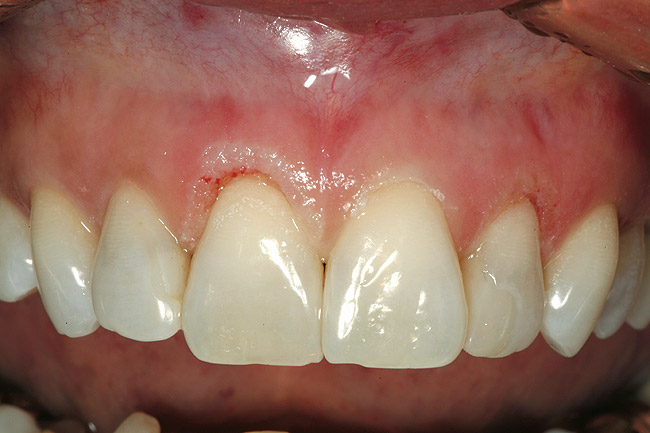

Figure 8  After initial closed-flap bony correction, a full-thickness mucoperiosteal flap was raised to visualize the accuracy of the osseous correction and observe the tooth surface and condition of the bony crest as a result of the procedure. It can be seen that the surface of the root is unscathed. The osseous crest was accurately repositioned 3 mm apically from the restorative margin, following its exact contour.

Figure 8

Figure 9  Facial view of tooth Nos. 7 through 10 after completion of the surgical phase of treatment.

Figure 9